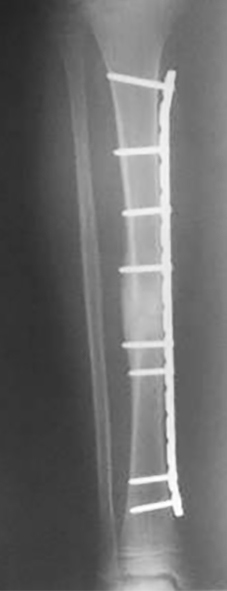

Se utilizaron placas bloqueadas LCP (Synthes, Paoli, PA) en seis pacientes y en dos pacientes placas de reconstrucción bloqueadas (Synthes, Paoli, PA) acorde al largo del hueso (placas largas). En una primera instancia se colocaron fijadores externos en las fracturas expuestas de seis pacientes. Se realizaron limpiezas quirúrgicas en promedio de 2 por paciente (rango: 1-5) y una vez que las partes blandas lo permitieron, se colocó la placa bloqueada. El tiempo promedio para la realización de la cirugía definitiva fue de 8 (rango: 3 - 25) días. En cuatro pacientes se realizó un abordaje antero-interno y se colocó la placa en el sector interno. En dos pacientes se realizó un abordaje externo y se colocó la placa en dicho sector. En otros dos pacientes se realizó un abordaje externo proximal y otro anterior distal, deslizándose la placa desde el sector externo al sector anterior, previo contorneado de la paca. Solo se pudo realizar la técnica MIPO en dos pacientes.

Del total de pacientes, cuatro tuvieron resultados excelentes y cuatro satisfactorios. Todas la fracturas consolidaron en un tiempo medio de 15 semanas (rango: 12-21). Se realizó solo aporte de injerto de esponjosa en un paciente con una pseudoartrosis atrófica tratada previamente con EEF. Todos los pacientes presentaron una movilidad completa de la rodilla y cuello de pie indolora, sin manifestar alteraciones de la marcha y no se encontraron deformidades angulares (mediante examen clínico y radiografías) ni discrepancias en los miembros inferiores significativas con un promedio de hipercrecimiento de 1,6 (rango: -5 a 10) mm. Se autorizó el apoyo parcial a las 5 semanas (rango: 4-8 semanas) y el apoyo total a las 10 (rango: 8 – 13) semanas. Como complicaciones menores, cuatro pacientes presentaron dolor en el implante, sobre todo en aquellos pacientes donde se colocó la placa en el sector interno y en la configuración externa / anterior, sin significado funcional, coordinándose para retirar las mismas (Tabla 1) (Tabla 2) (Figura 1) (Figura 2).